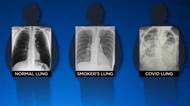

Americký lékař sdílel rentgenové snímky, ze kterých je patrný rozdíl mezi plícemi plně očkovaného a neočkovaného člověka. Orgány nakažené osoby, která nemá potřebné protilátky, výrazně změnily strukturu. Naopak plíce očkovaného pacienta obvykle známky nákazy téměř nevykazovaly. Lékař doufá, že fotografie pacienty motivuje k podstoupení vakcinace.